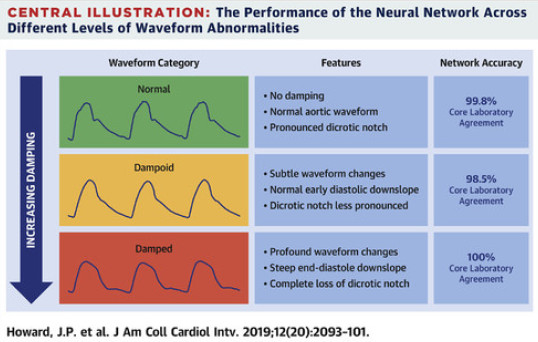

Cardiac pressure waveforms - LINK

The identification of adverse pressure signals during an angiogram, termed "damping", is necessary to maintain safety and the accuracy of coronary physiology measurements. James developed an AI which is able to accurately monitor these signals.